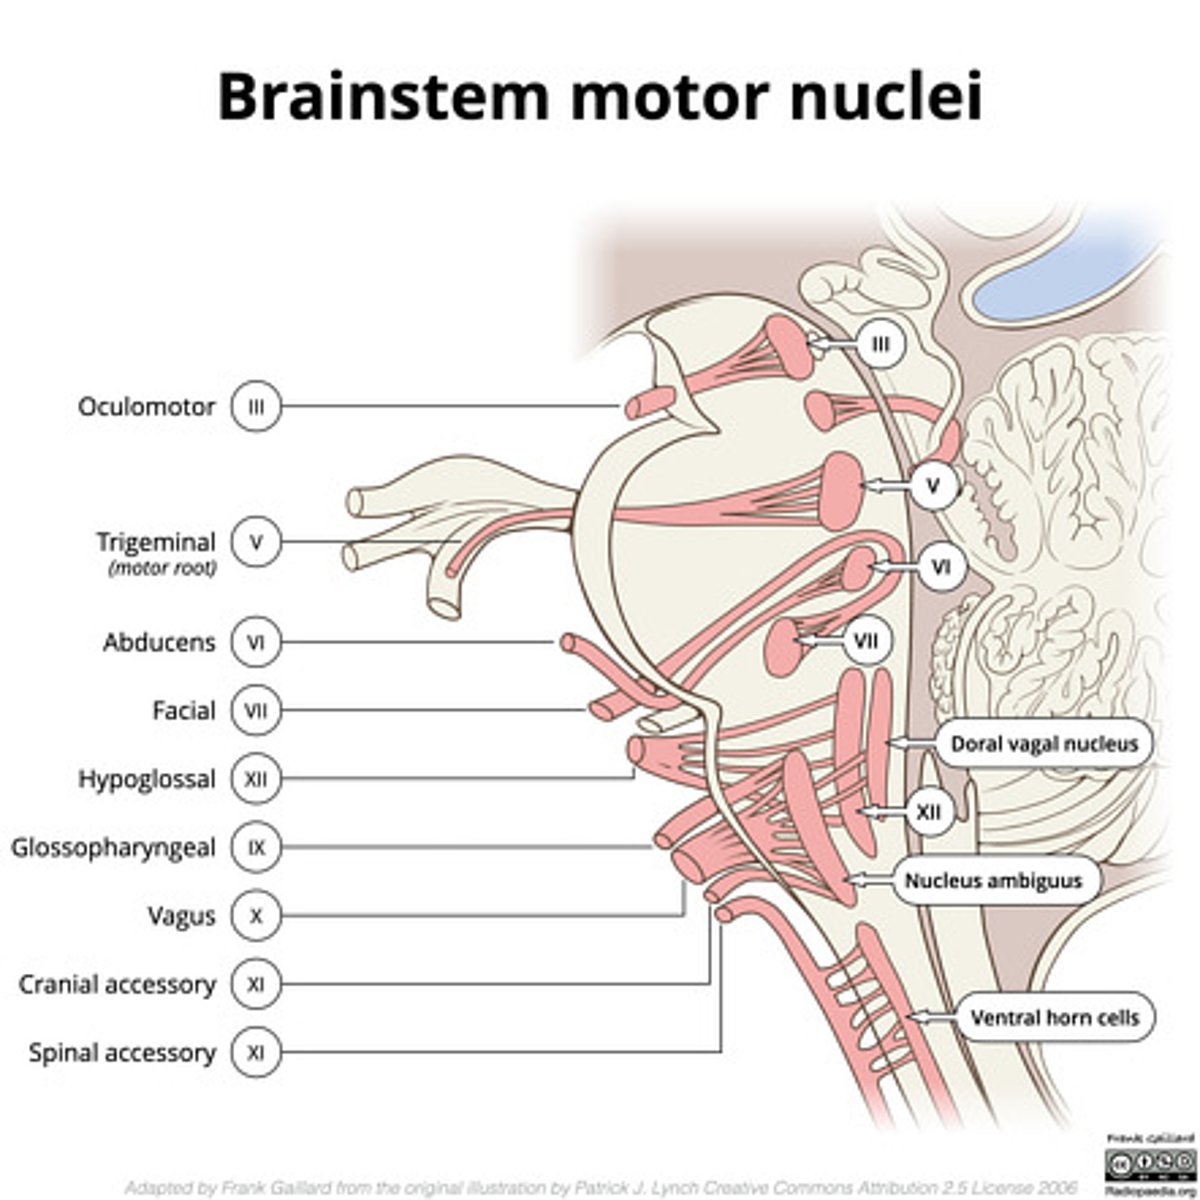

What are the structures of the brainstem?

1. mesencephalon (midbrain)

2. pons

3. medulla oblongata

What cranial nerve nuclei are in the tegmentum pons?

1. CN V (5)

2. CN VI (6)

3. CN VII (7)

4. CN VIII (8)

What nuclei are at the pontomedullary junction?

1. SVE of CN VI

2. SVE of CN VII (facial)

What cranial nerves reside in the medulla?

1. CN IX

2. CN X

3. CN XI

4. CN XII